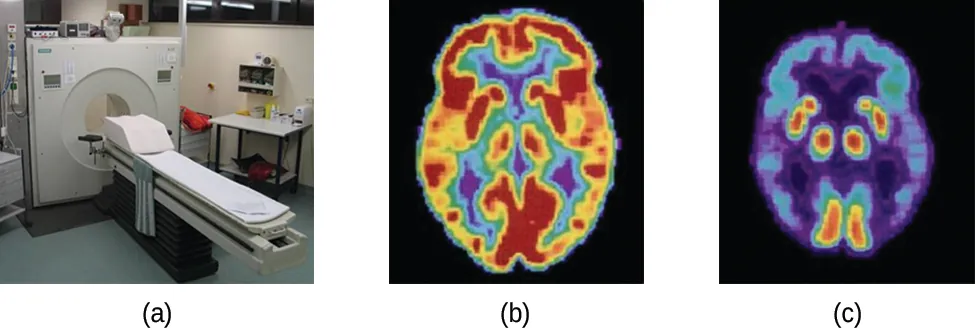

La tomografía por emisión de positrones (Positron Emission Tomography, PET) utiliza la radiación para diagnosticar y hacer seguimiento de las enfermedades, además de supervisar los tratamientos médicos, al revelar cómo funcionan las partes del organismo del paciente (Figura 21.8). Para realizar una PET, se produce un radioisótopo emisor de positrones en un ciclotrón y luego se une a una sustancia que utiliza la parte del cuerpo que se investiga. Este compuesto "marcado", o radiotrazador, se introduce en el paciente (se inyecta por vía intravenosa o se respira en forma de gas), y la forma en que lo utiliza el tejido revela cómo funciona ese órgano u otra zona del cuerpo.

Se muestran tres imágenes marcadas como "a", "b" y "c". La imagen a muestra una máquina con una abertura redonda conectada a una mesa de examen. La imagen b es la exploración médica de la parte superior de la cabeza de una persona y muestra grandes manchas de color amarillo y rojo y otras más pequeñas de color azul, verde y morado. La imagen c también es la exploración médica de la parte superior de la cabeza de una persona, aunque coloreada en su mayor parte en azul y púrpura, con manchas muy pequeñas de rojo y amarillo.

Figura 21.8 Un tomógrafo (a) utiliza la radiación para proporcionar una imagen del funcionamiento de una parte del cuerpo del paciente. Las exploraciones que produce se utilizan para obtener imágenes de un cerebro sano (b) o para diagnosticar afecciones médicas como la enfermedad de Alzheimer (c) (créditos a: modificación del trabajo de Jens Maus).

Por ejemplo, el F-18 se produce por bombardeo de protones de 18O ( 818O + 11p 918F + 01n )( 818O + 11p 918F + 01n ) e incorporada a un análogo de la glucosa, denominado fludeoxiglucosa (FDG). La forma en que el organismo utiliza la FDG suministra información de diagnóstico fundamental; por ejemplo, dado que las neoplasias utilizan la glucosa de manera distinta a los tejidos normales, la FDG puede revelar estas neoplasias. El 18F emite positrones que interactúan con los electrones cercanos, lo que genera una ráfaga de radiación gama. El tomógrafo detecta esta energía y la convierte en una imagen detallada, tridimensional y a colores que muestra el funcionamiento de esa parte del organismo del paciente. Distintos niveles de radiación gama emiten diferentes cantidades de brillo y colores en la imagen, lo que el radiólogo puede interpretar para revelar lo que sucede. Los tomógrafos de emisión de positrones son capaces de detectar cardiopatías, diagnosticar la enfermedad de Alzheimer, indicar la parte del cerebro afectada por la epilepsia, revelar el cáncer, mostrar en qué fase se encuentra y cuánto se ha extendido, y si los tratamientos son eficaces. A diferencia de la imagen de resonancia magnética y los rayos X, que muestran únicamente el aspecto de algo, la gran ventaja de la PET es que muestra cómo funciona algo. En la actualidad, la PET se realiza junto con la tomografía computarizada.